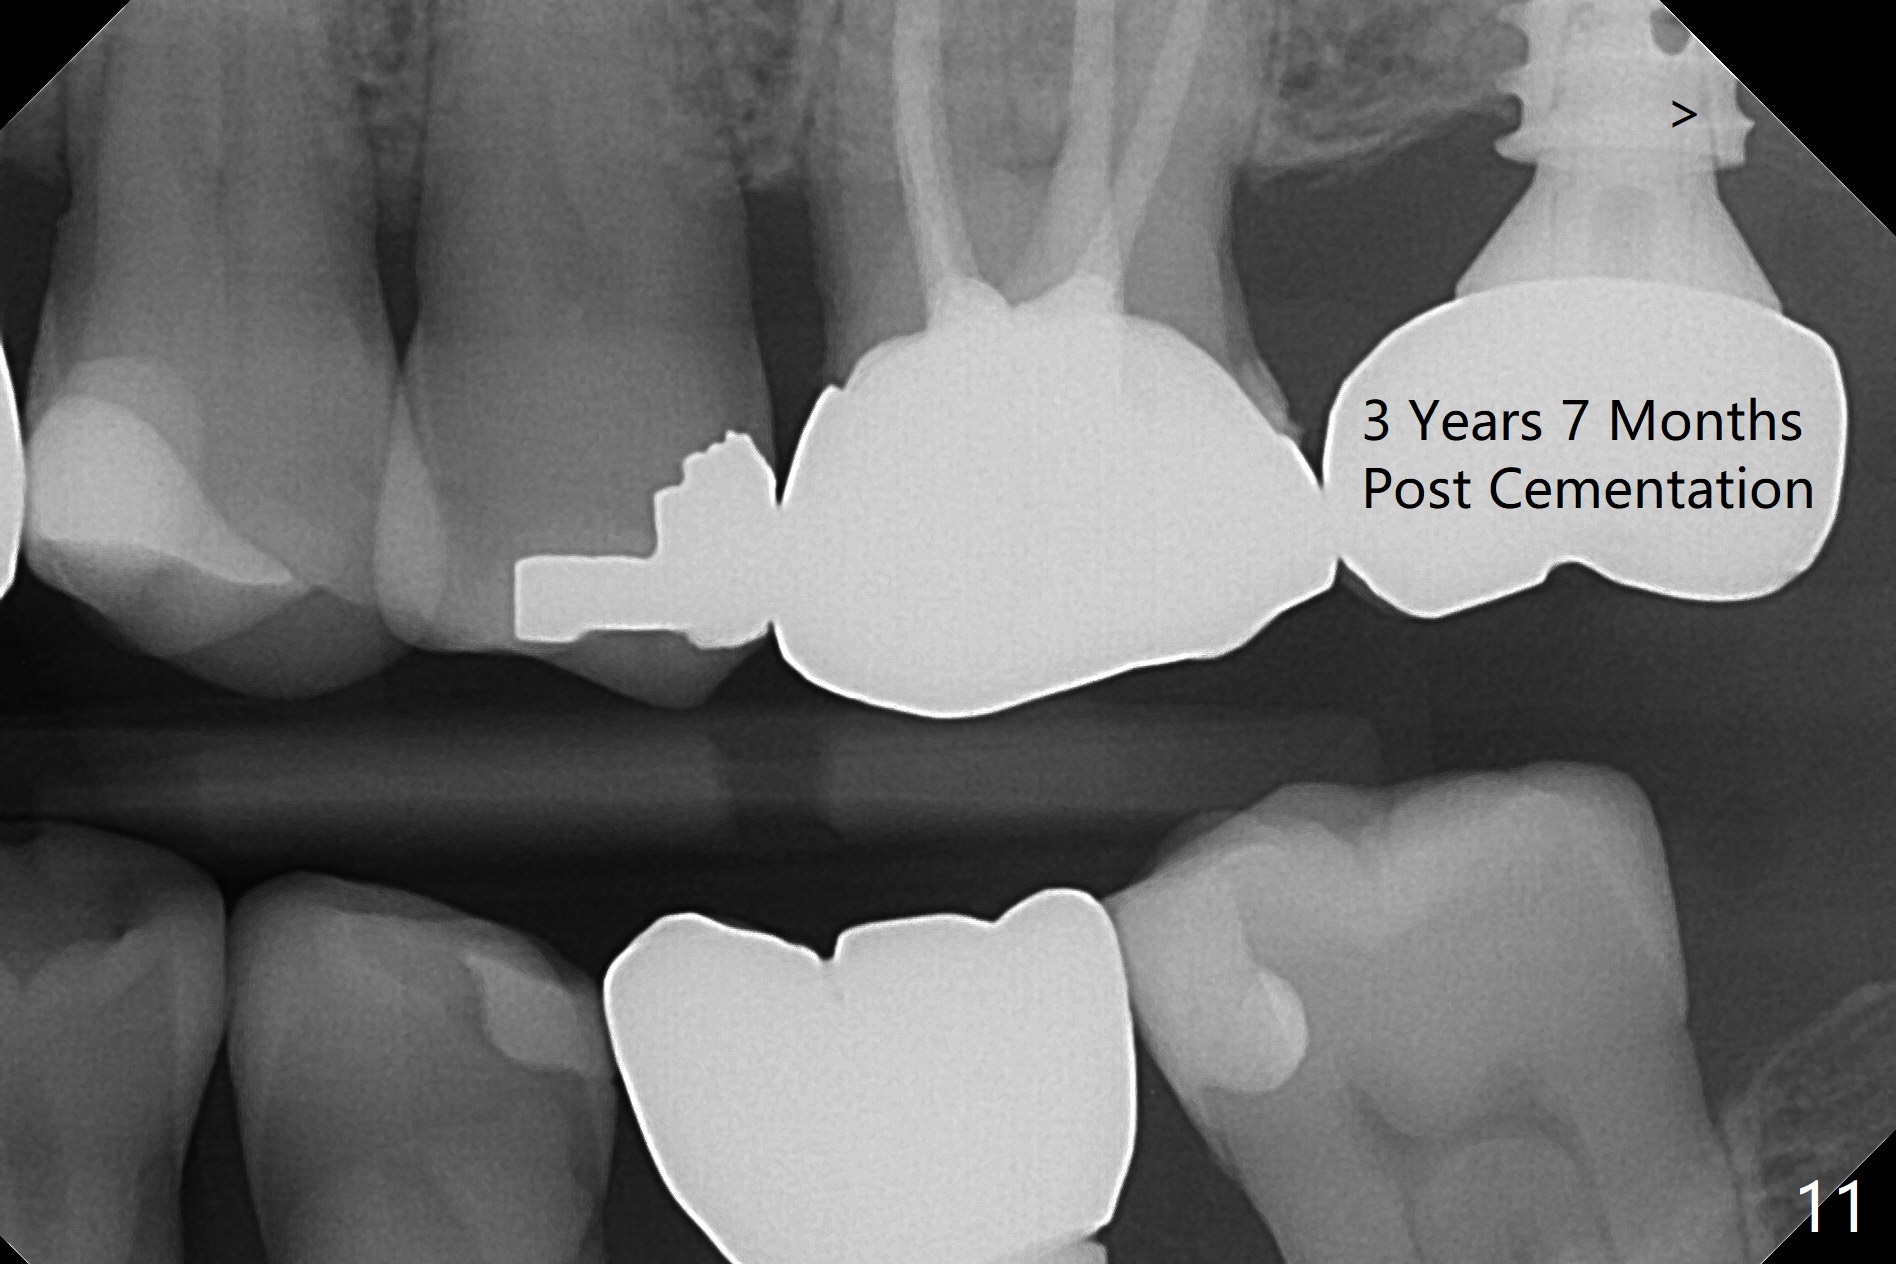

The ridge is pointed at the site of #15 (Fig.1). A 1.2 mm initial drill is used to start osteotomy for 10 mm, followed by an incision over the ridge mesiodistally for ~ 8 mm. After tapping the #15 C blade, the 1st Bone Expander 1.0/1.6 mm) is inserted for ~ 11 mm (Fig.2, 20 Ncm). Bone expansion continues until #4 Expander (2.4/3.7 mm, Fig.3). When 4x11 mm and 4.5x11 mm dummy implants are placed (Fig.4), insertion torque remains 20 Ncm. Following placing allograft with 3-4 amalgam carriers, a 5x11 mm IBS implant is placed with 20 Ncm (Fig.5,6). In fact the implant turns when an abutment is placed. When the implant is re-inserted, torque decreases to 10 Ncm. Instead a healing screw is placed. The low torque value is due to soft bone and failure to underprep. #4 Expander (Fig.3) seems larger than 4.5 mm implant (Fig.4). #3 Expander (1.7/3.1 mm) should have been used prior to definitive implant placement. The implant appears to have osteointegrated 3 months postop (Fig.7); impression is taken. The bone density at the crest increases 1.5 years post cementation (Fig.8 *, as compared to Fig.6), although there is mild bone loss. Implant placement should be deep when bone expansion is carried out. The tooth #14 develops a buccal fistula, corresponding to periapical radiolucency of the mesiobuccal root (Fig.9 white >). The abutment of #15 may be incompletely seated (black <). PA taken when RCT of #14 is finished does not show the incomplete seating of the abutment (Fig.10). Since there appears no history of abutment screw loosening, the abutment is not reseated when #14 is prepared for crown. Recall 3 years 7 months post cementation shows incomplete seating of the abutment (Fig.11 >). After crown proximal reduction (Fig.12 *) and clockwise turn of the crown, the abutment appears to be completely seated. When the case returns from lab, the separate crown and abutment cannot be connected to the fixture because of soft tissue adaptation and change in a month. The abutment is reseated to the fixture analog in the model and the crown is recemented with temp bond (in case of misalignment) while making sure that the crown has the best proximal contact with the neighboring crown. With the abutment and crown in a unit, it is much easier to reseat the abutment with normal proximal contact. The torque is 20 Ncm. The access hole is closed with Cavit.